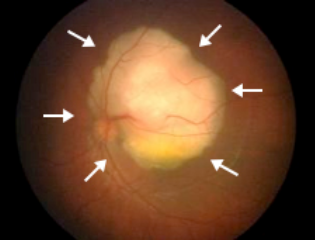

正常情况下视网膜的反光是橘红色的,也就是照片中的“红眼”,但对视网膜母细胞瘤的患儿来说,由于肿瘤的存在,他们瞳孔反射的光却是白色↓↓↓

(右眼瞳孔发白)